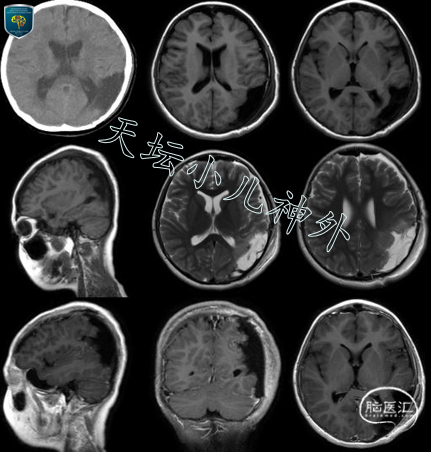

门诊查体示:神清、言语略迟缓,自主体位,生长发育正常,余神经系统查体阴性。头颅CT显示:左侧颞顶枕叶占位,星形细胞瘤可能性大。头部MRI显示:左侧颞顶枕片状异常信号,边界不清,长T1长T2,左侧脑室轻度受压变形,无显著强化,FLAIR像呈混杂信号,DWI像无明显弥散受限,星形细胞瘤?(图1)。MRS显示:病灶感兴趣区Cho/Cr为2.088,NAA/Cr为0.7;正常对照区域Cho/Cr为0.805,NAA/Cr为2.0。Cho峰升高,NAA峰下降,提示低级别胶质瘤。24小时视频脑电显示为儿童正常脑电图。

图1 术前头颅CT:左侧颞顶枕叶占位,星形细胞瘤可能性大;头部MRI显示:左侧颞顶枕片状异常信号,边界不清,长T1长T2,左侧脑室轻度受压变形,无显著强化,FLAIR像呈混杂信号,DWI像无明显弥散受限,星形细胞瘤?